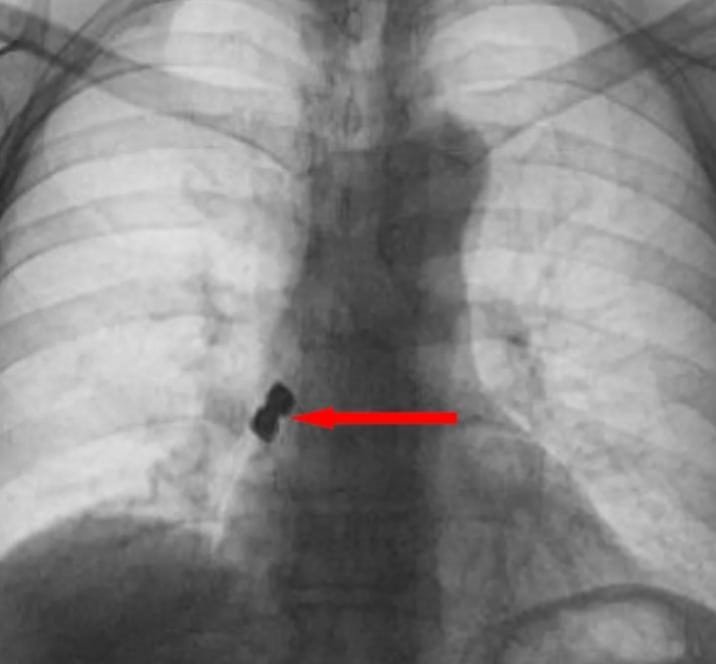

Afyonkarahisar'da 56 yaşındaki bir şahıs tedavi için gittiği diş kliniğinde yanlışlıkla 2 adet implantı (diş kaplaması) yuttu. Yuttuğu dişler akciğerine kaçarak sağ nefes borusunu tıkayan 56 yaşındaki şahıs ölümden döndü.

Olay Emirdağ ilçesinde meydana geldi. İddiaya göre, Belçika'nın Brüksel kentinde yaşayan 56 yaşındaki D.K., isimli gurbetçi vatandaş implant diş tedavisi için Emirdağ'daki bir kliniğe gitti. Operasyon esnasında birbirine yapışık halde olan 2 adet implant bir anda hastanın dişinden düştü. İmplantlar ardından hasta yutkununca akciğerlere kaçıp sağ nefes borusunu tıkadı. Nefes almakta zorlanan D.K., ardından Emirdağ Devlet Hastanesi'ne kaldırıldı. Burada yapılan müdahalenin ardından D.K., Afyonkarahisar kent merkezindeki bir hastaneye sevk edildi. Burada D.K.'nın akciğerine kaçan implantlar cerrahi operasyona gerek kalmadan, bronkoskopi yöntemi adı verilen tıbbi müdahale ile çıkarıldı. İmplant yüzünden ölüm tehlikesi atlatan D.K., birkaç gün hastanede kaldıktan sonra taburcu edildi.